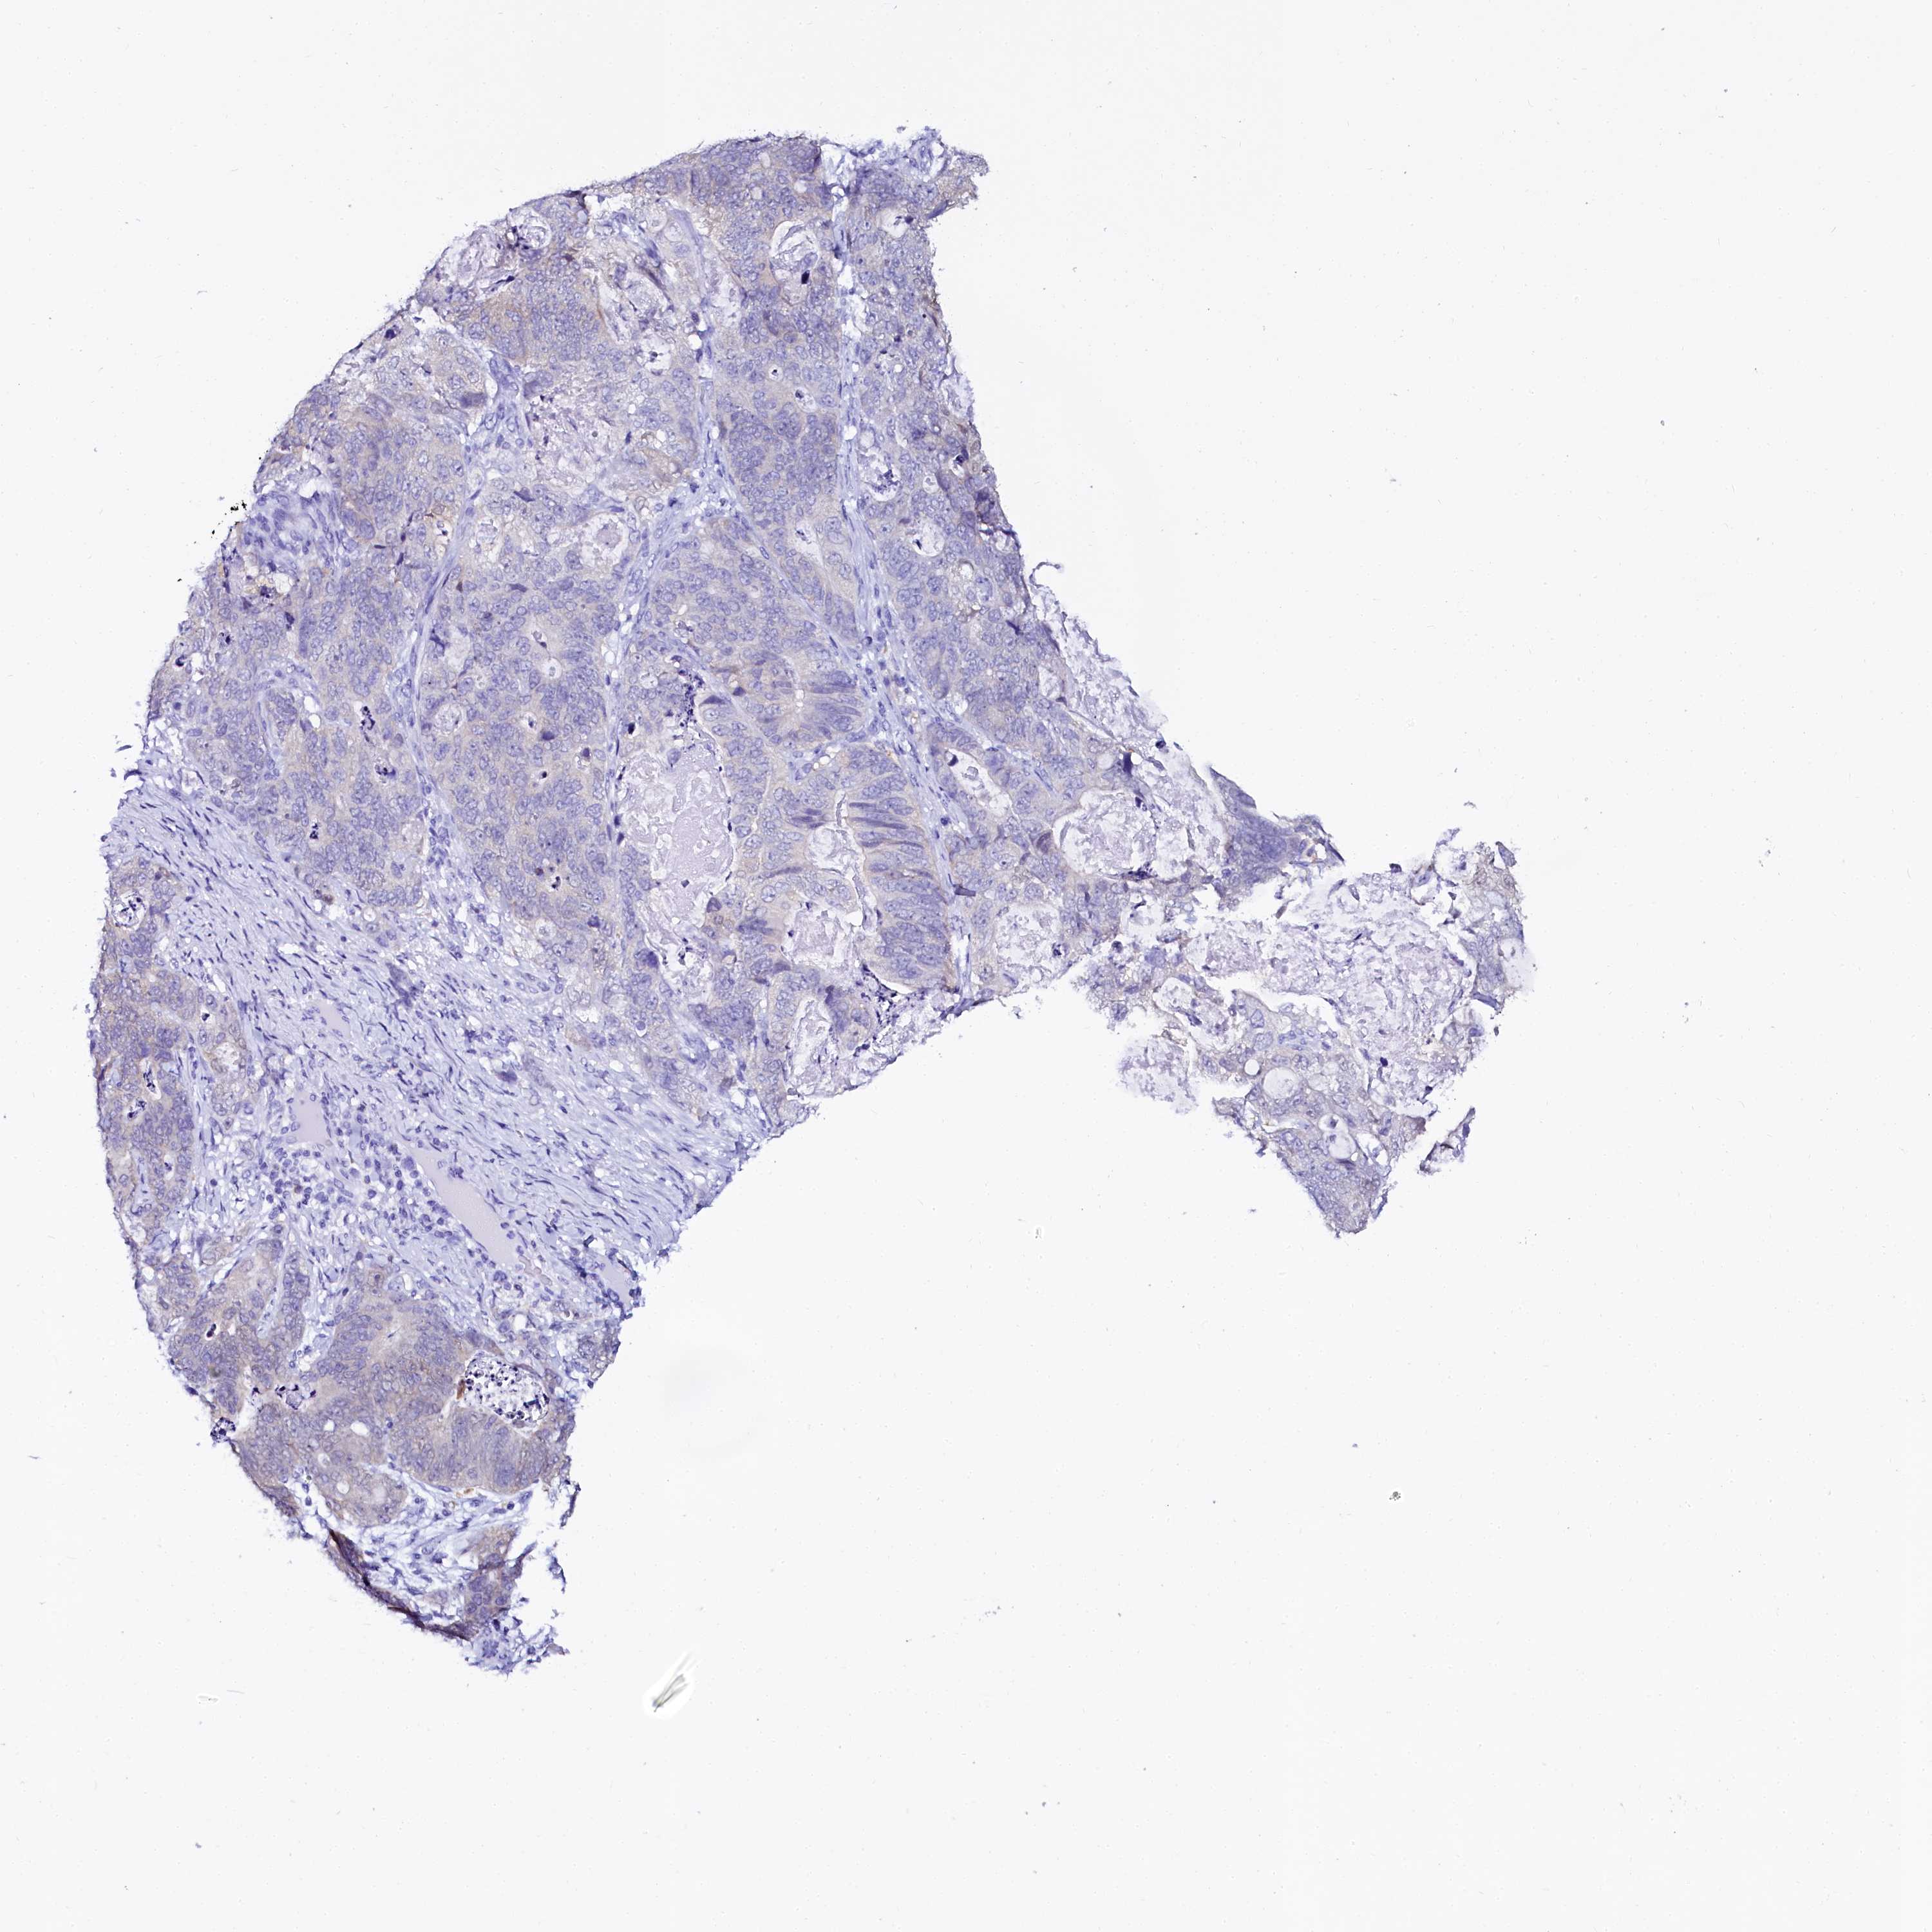

STOMACH CANCER - Protein expressioni

A mouse-over function shows sample information and annotation data. Click on an image to view it in a full screen mode. Samples can be filtered based on level of antibody staining by selecting one or several of the following categories: high, medium, low and not detected. The assay and annotation is described here.

Note that samples used for immunohistochemistry by the Human Protein Atlas do not correspond to samples in the TCGA dataset.

Antibody stainingi

Antibody staining in the annotated cell types in the current human tissue is reported as not detected, low, medium, or high, based on conventional immunohistochemistry profiling in selected tissues. This score is based on the combination of the staining intensity and fraction of stained cells.

Each image is clickable and will lead to virtual microscopy that enables deeper exploration of all samples and also displays staining intensity scores, fraction scores and subcellular localization as well as patient and tissue information for each sample.

Antibody HPA040260

Antibody HPA040621

Staining

High

Medium

Low

Not detected

Intensity

Strong

Moderate

Weak

Negative

Quantity

>75%

75%-25%

<25%

None

Location

Nuclear

Cytoplasmic/membranous

Cytoplasmic/membranous,nuclear

Adenocarcinoma, NOS